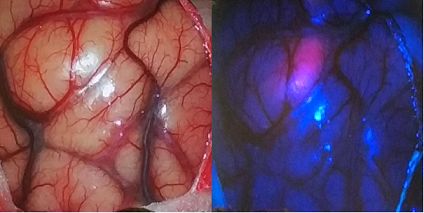

▲ (左侧)手术视野下暴露的脑组织,很难凭肉眼判断肿瘤的具体部位;(右侧)使用光敏剂照射激发光的方法就能立刻发现肿瘤的所在位置